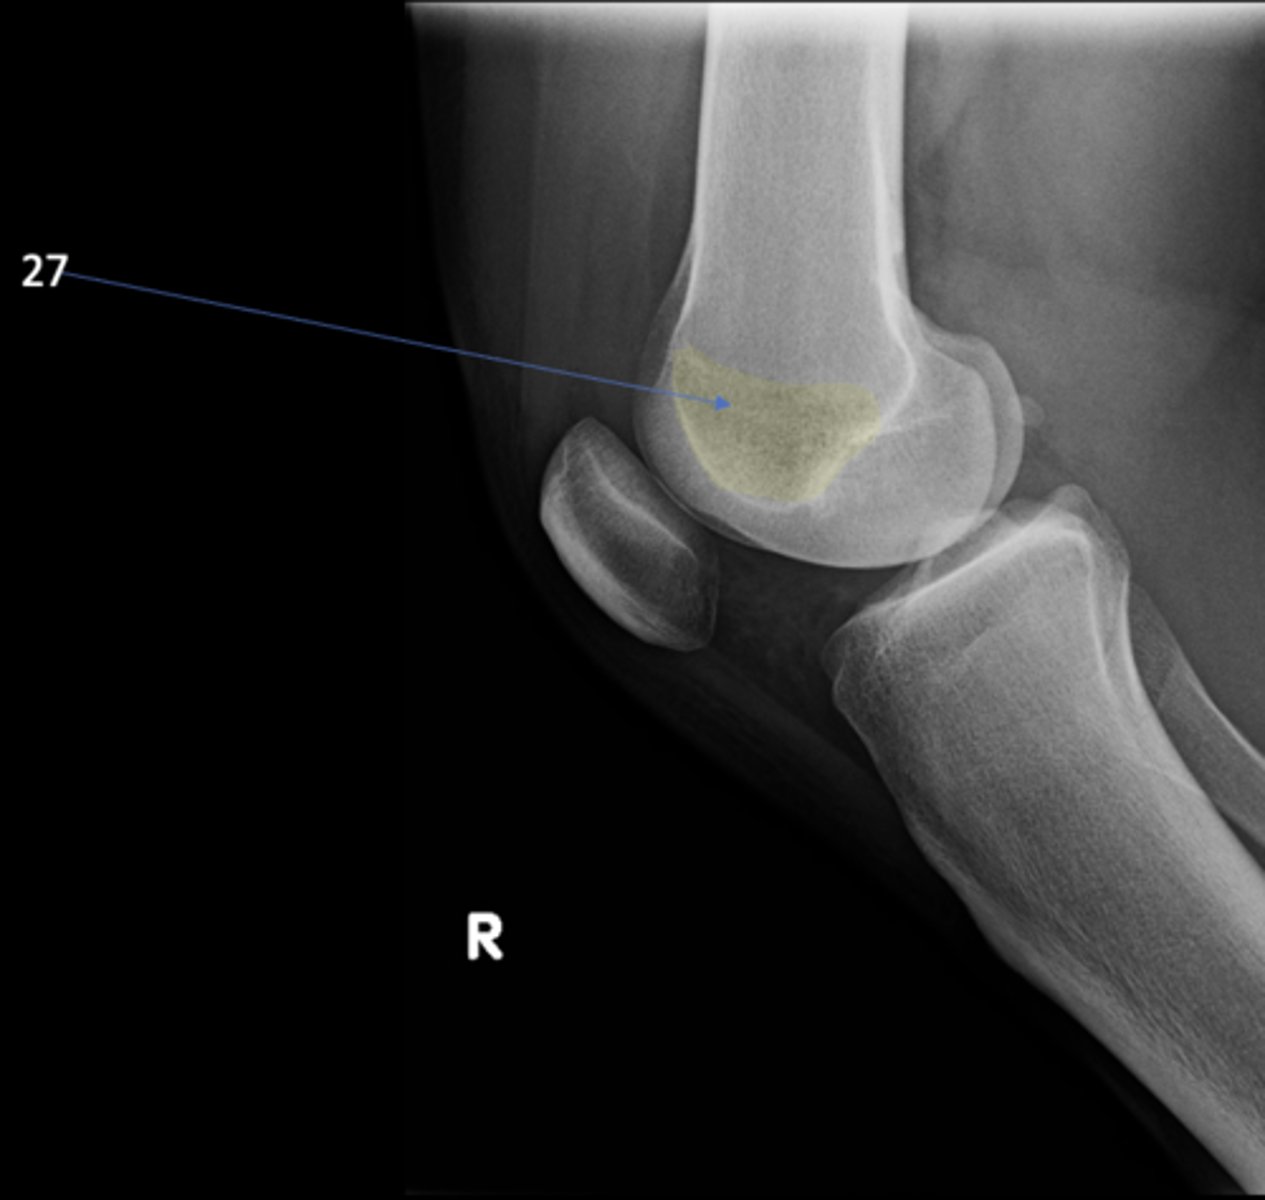

67

Right lateral knee

View?

<p>View?</p>

Ludloff's spot/patch

ID 27

<p>ID 27</p>